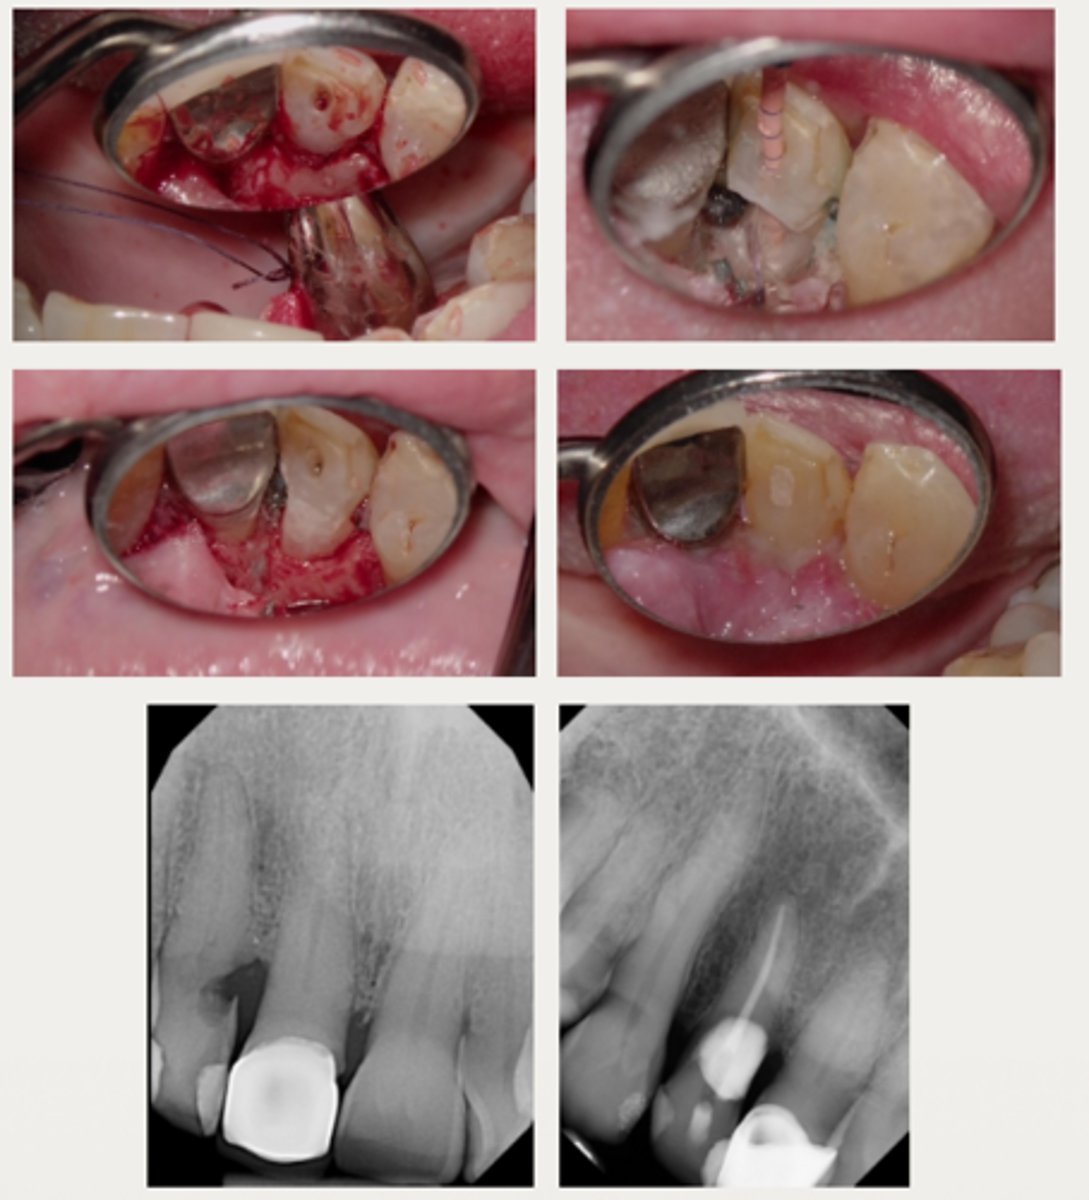

External surgical repair only

These are a part of which treatment for External Cervical Resorption (ECR)?

For lesions that are accessible through raising a flap and that are unlikely to have pulpal involvement after removal

- Raise a flap

- Complete debridement of the resorptive lesion

- Tx with 90% trichloroacetic acid (TCA) or 5.25% NaOCl

- Restoration of defect with resin-modified glass ionomer (Geristore) or Biodentine

- Flap closure and suturing

External surgical repair with RCT

For lesions with a large portal of entry where the resorptive defect would be accessible by raising a flap without having to remove excessive marginal bone:

- Same as the external repair only approach

- RCT may be completed before or after the repair, if care is taken to prevent canal blockage when restoring the defect first

Internal repair with RCT

For lesions with a small portal of entry where the resorptive lesion is in close approximation to the chamber/canals

- Root canal therapy is initiated

- Resorptive lesion is debrided through the access cavity using 90% TCA or NaOCl

- Root canal therapy is completed

- Resorptive defect is restored using RMGI, Biodentine, or Bioceramics (ERRM) depending on the level and extent of the perforation